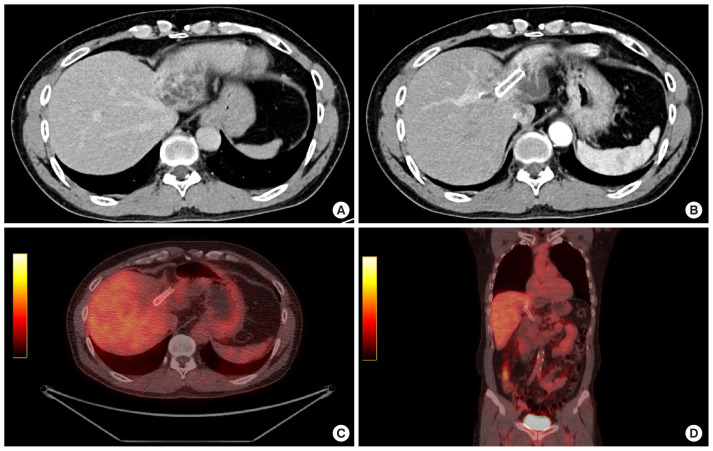

本病例研究探讨了自体细胞因子诱导杀伤(CIK)细胞免疫疗法对一名49岁男性无法手术的IIIb期胆管癌患者的有效性,该患者的特征是免疫细胞中钠依赖性维生素C转运蛋白-2 (SVCT2)水平高。尽管化疗后最初缺乏肿瘤缩小,但患者在接受放射和质子治疗后,肿瘤标志物显著减少,肿瘤稳定。随后,CIK细胞治疗联合大剂量维生素C, 6年52次。患者肿瘤缩小,诊断后7年10个月未检测到肿瘤活动,表明长期预后成功,无复发。这项研究表明,CIK细胞治疗,特别是对于SVCT2水平升高的患者,可能为胆管癌和潜在的其他癌症提供有希望的辅助治疗。需要进一步的研究来验证SVCT2作为CIK细胞治疗有效性的生物标志物。

This case study explores the effectiveness of autologous cytokine-induced killer (CIK) cell-based immunotherapy in a 49-year-old male patient with inoperable stage IIIb cholangiocarcinoma, characterized by high levels of the sodium-dependent vitamin C transporter-2 (SVCT2) in immune cells. Despite an initial lack of tumor reduction following chemotherapy, the patient showed a significant decrease in tumor markers and stabilization of the tumor after undergoing radiation and proton therapy. Subsequently, CIK cell therapy, combined with high-dose vitamin C, was administered 52 times over 6 years. The patient's tumor size reduced, and no cancer activity was detected for 7 years and 10 months post-diagnosis, indicating a successful long-term outcome without recurrence. This study suggests that CIK cell therapy, particularly in patients with elevated SVCT2 levels, may offer a promising adjuvant treatment for cholangiocarcinoma and potentially other cancers. Further research is needed to validate SVCT2 as a biomarker for the effectiveness of CIK cell therapy.